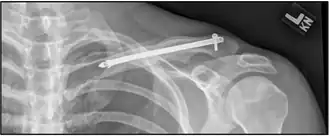

X-ray of the above comminuted fracture treated with an intramedullary fixation device

In children, breaks in the middle of the clavicle treated with surgery resulted in faster recoveries but more complications.[14] The evidence for different types of surgery for breaks of the middle part of the clavicle is poor as of 2015.[15]